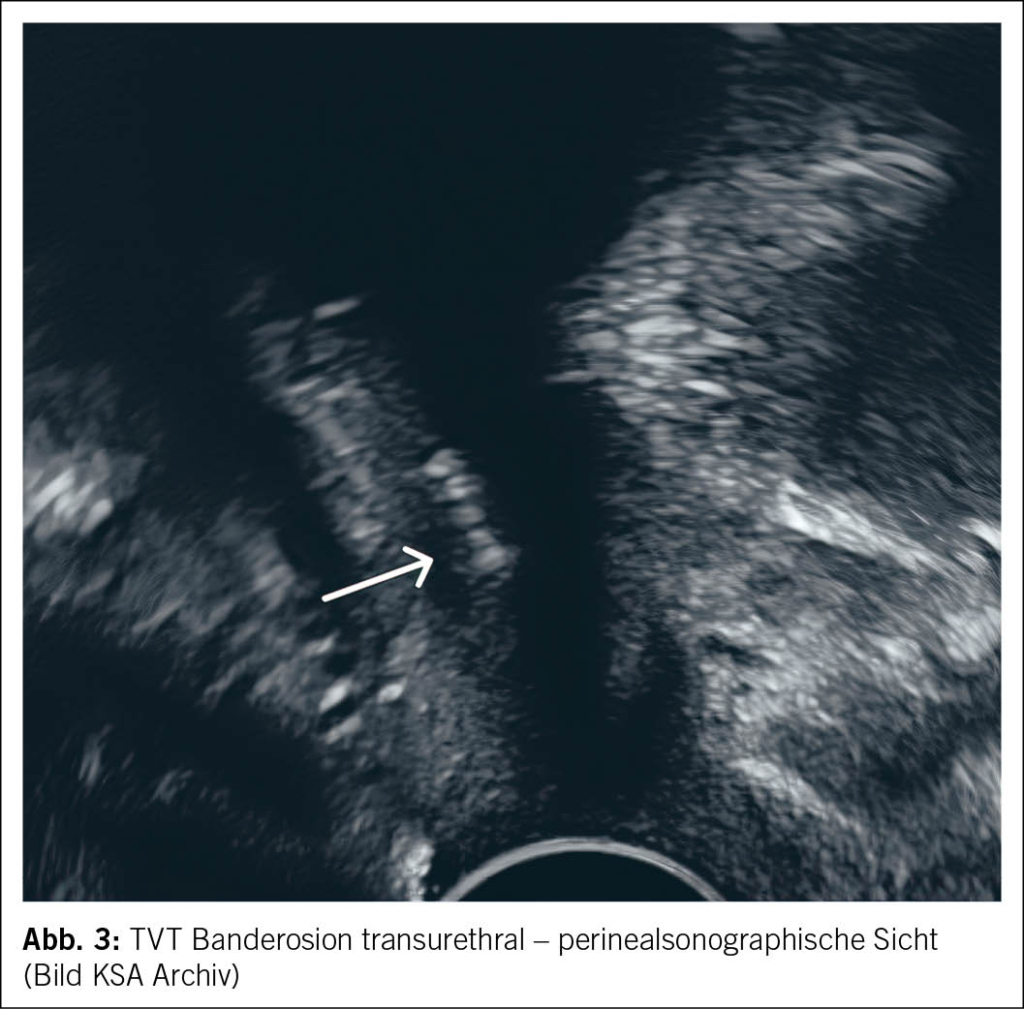

Bei vermuteter postoperativer Komplikation sind eine gründliche Anamnese und körperliche Untersuchung essenziell. Die Perinealsonographie gilt als Goldstandard der Bildgebung zur Diagnostik postoperativer Komplikationen. Besteht der Verdacht auf eine Erosion in Blase oder Harnröhre, sollte eine Zystoskopie durchgeführt werden. In unklaren Fällen kann zusätzlich eine Magnetresonanztomographie (MRT) des Beckenbodens zur weiteren Abklärung eingesetzt werden. Ein präzises Verständnis des ursprünglichen Eingriffs sowie der Lage des Bandes ist entscheidend für die Therapieplanung (3, 4) (Abb. 3 und Abb. 4).